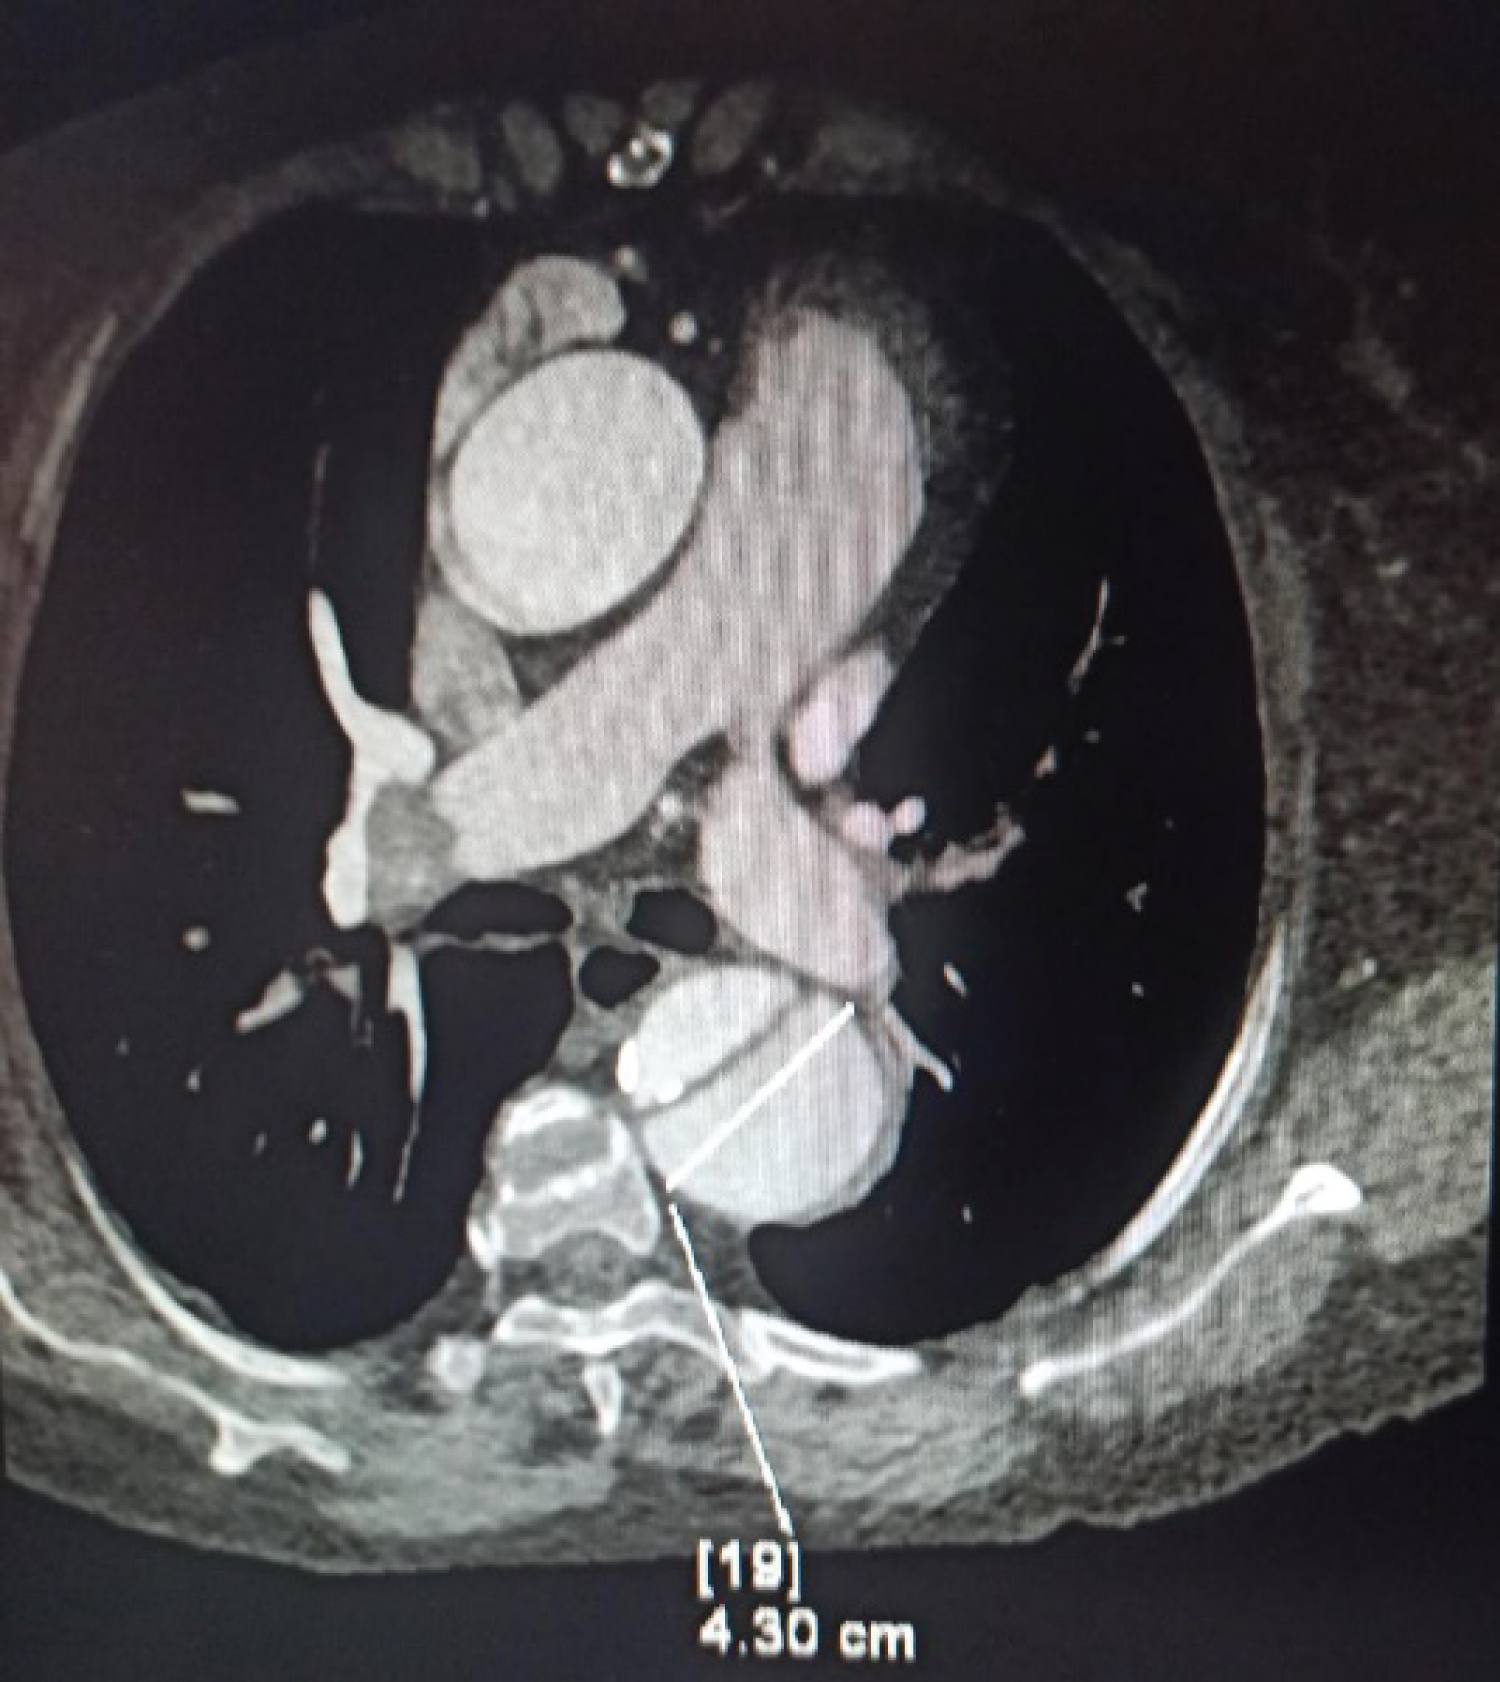

A 68-year-old female patient came to the emergency department with an alleged history of falls at level ground. She was evaluated at another hospital, where an echocardiography finding revealed-a dissection flap in the descending thoracic aorta, moderately severe aortic regurgitation, mildly dilated left ventricle with moderate systolic dysfunction (LVEF-40%), and moderate global hypokinesia. For this above-mentioned echocardiographic finding, she was referred to our hospital. Two years ago, she was diagnosed with dilated cardiomyopathy (DCMP), for which she is taking metoprolol (50 mg) and aldactone. Also, she was known hypertensive for the last 5 years, for which she is taking the tablet losartan (80 mg). Her chest X-ray finding showed cardiomegaly and mediastinal widening (Figure 1), which was consistent with echocardiographic findings and an X-ray of the left hip revealed an inter-trochanteric fracture of the left femur. A CT angiogram (Figure 2) was done, as advised by the cardiothoracic team, which showed type B aortic dissection extending from the distal to left subclavian artery till bifurcation of the aorta and extending into the left common iliac artery with a total aortic diameter of more than 40 mm and patent false lumen of more than 22 mm showing no signs of rupture/impending rupture. Considering her age, and clinical and medical conditions, the cardiothoracic team has advised conservative management for dissection and stratified very high risk for any other surgical procedures. Since the management of an inter-trochanteric fracture is considered urgent and delaying it for more than 48 h increases the risk for both morbidity and mortality, the patient was posted for hip fracture surgery and an aesthesiologists were informed of the same.

Figure 1: Chest X-ray PA view. View Figure 1

With the above patient, our main concern was the incidence of acute aortic dissection which can become fatal at any time, during the intraoperative period due to surgical stress and any hemodynamic derangement, leading to sudden death. Aortic dissection is the most common acute aortic syndrome and is considered a medical and surgical emergency. Aortic dissection is classified by Stanford and DeBakey based on its anatomy, as shown in Figure 3 [2]. Type A aortic dissections are always considered a surgical emergency, while type B aortic dissections can be managed conservatively or with selective surgical interventions as the case with our patient [3]. Our patient had an incidental finding of aortic dissection in her regular follow-up echocardiography performed for DCMP. In such asymptomatic cases, echocardiography may not be available for all patients, one may use chest X-rays. In plain radiography, mediastinal widening is the most common abnormality seen in approximately 80% of patients, while other findings include - double aortic contour, irregular aortic contour, or inward displacement of atherosclerotic calcification [4].